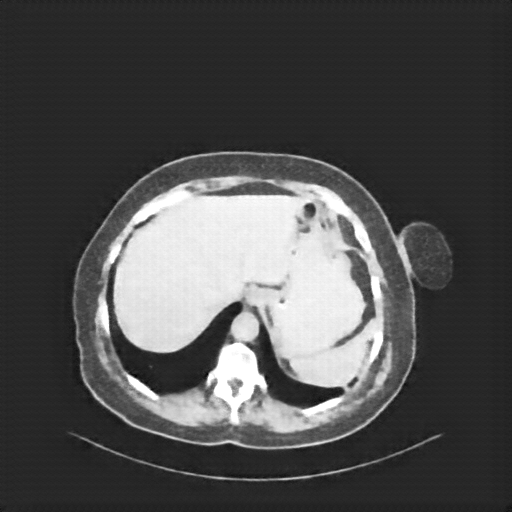

Original VENOUS CT scan

Full window (WL 1023.5, WW 4095 β†’ Low βˆ’1024, High +3071)

Actual HU range: [-160.0, 240.0]